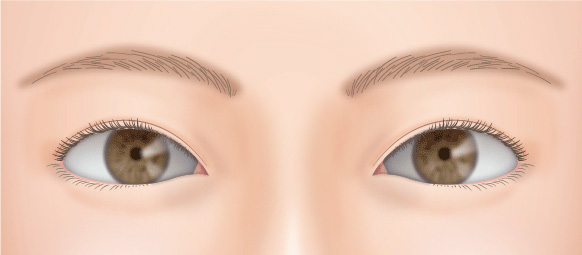

二重の幅が広くなり過ぎて、いかにも整形っぽい目になることがあります。

無理に幅広の二重を作った場合、腫れが半年以上も続き、ハム目のようになる場合があります。